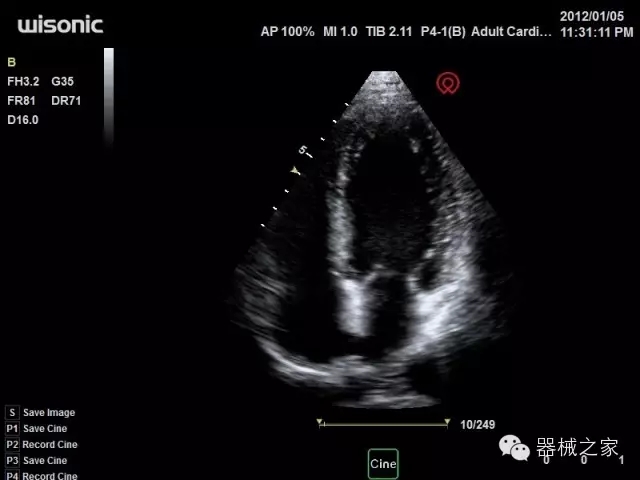

品牌:華聲醫(yī)療(WISONIC)

深圳華聲醫(yī)療技術(shù)有限公司成立于2012年,位于深圳南山西麗湖畔。是一家從事醫(yī)療設(shè)備研發(fā)、制造、營(yíng)銷的新興高新技術(shù)企業(yè),目前提供生命信息支持、數(shù)字便攜彩超、移動(dòng)醫(yī)療服務(wù)三個(gè)方面的業(yè)務(wù)解決方案。公司核心創(chuàng)始人均為醫(yī)療設(shè)備行業(yè)領(lǐng)軍人物,在醫(yī)療行業(yè)服務(wù)時(shí)間平均在10年以上,對(duì)行業(yè)和產(chǎn)品積累了深刻的認(rèn)識(shí)。公司在創(chuàng)立之初就有著長(zhǎng)遠(yuǎn)的戰(zhàn)略目標(biāo)和規(guī)劃,致力于醫(yī)療設(shè)備行業(yè)的細(xì)分市場(chǎng),貼近客戶所需,為大眾的健康提供更多關(guān)愛(ài)。

官方網(wǎng)站:www.wisonic.cn

經(jīng)典產(chǎn)品:四葉草

臨床圖片賞析

產(chǎn)品特點(diǎn)

·全球目前唯一一款配備主機(jī)雙探頭接口,整機(jī)重量(含電池)在5公斤以內(nèi)的便攜式彩超;

·一款互聯(lián)網(wǎng)彩超,只要有手機(jī)信號(hào)的地方就可以非常方便地實(shí)現(xiàn)遠(yuǎn)程會(huì)診和病案調(diào)取;

·鎂鋁合金外殼,堅(jiān)固可靠耐用;

·獨(dú)有的HoloTM PW 實(shí)時(shí)3取樣門(mén)PW成像技術(shù),精確進(jìn)行血管診斷;

·一鍵優(yōu)化B、Color、PW,Auto Doppler自動(dòng)識(shí)別血管位置、偏轉(zhuǎn)角度等,提高工作效率;

·30°超廣角精細(xì)偏轉(zhuǎn)成像技術(shù),更優(yōu)異的頻譜圖像;

·W+智能搜索引擎,快速尋找圖像;

·SSD、USB3.0保障開(kāi)機(jī)快,導(dǎo)出圖像更快,減少等待時(shí)間;

·WIFI、網(wǎng)口、3G,多重聯(lián)網(wǎng)方式,全天候保障云端備份,不再擔(dān)心圖像丟失;

CFDA注冊(cè)證編號(hào)

·粵械注準(zhǔn)201522231208